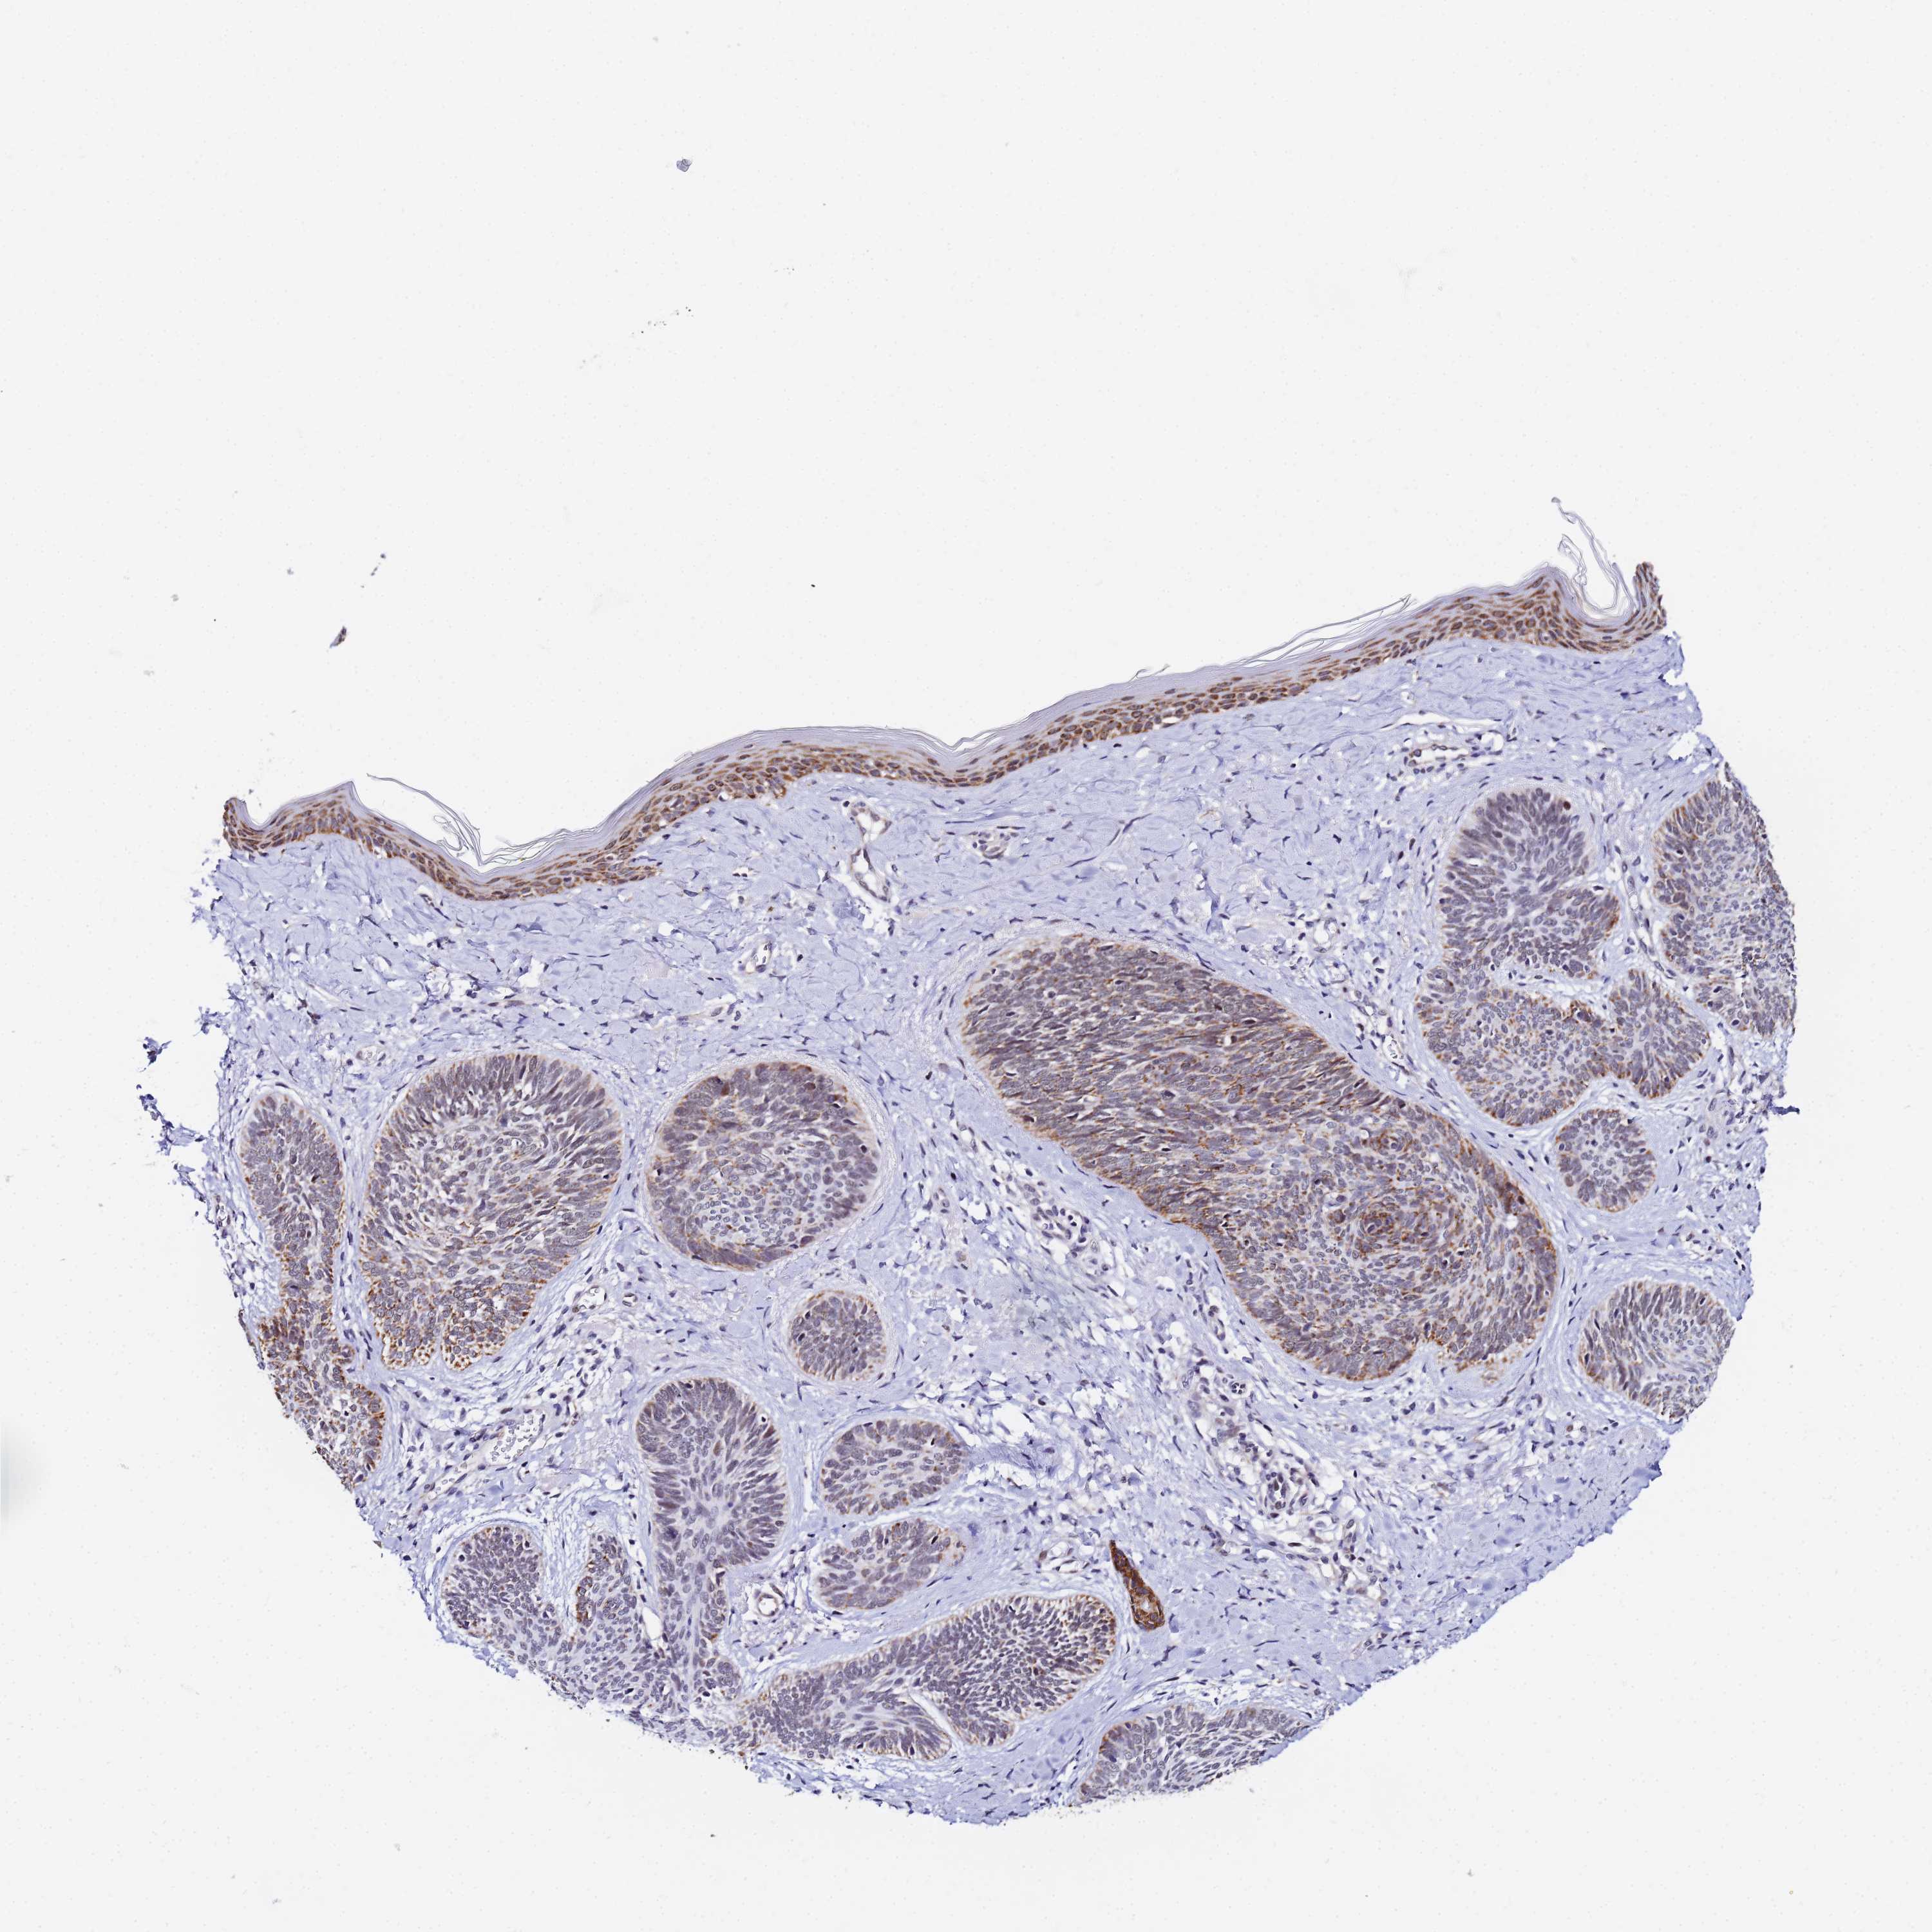

Basal cell and squamous cell cancer

SKIN CANCER - Protein expressioni

A mouse-over function shows sample information and annotation data. Click on an image to view it in a full screen mode. Samples can be filtered based on level of antibody staining by selecting one or several of the following categories: high, medium, low and not detected. The assay and annotation is described here.

Antibody stainingi

Antibody staining in the annotated cell types in the current human tissue is reported as not detected, low, medium, or high, based on conventional immunohistochemistry profiling in selected tissues. This score is based on the combination of the staining intensity and fraction of stained cells.

Each image is clickable and will lead to virtual microscopy that enables deeper exploration of all samples and also displays staining intensity scores, fraction scores and subcellular localization as well as patient and tissue information for each sample.

Antibody HPA043491

Staining

High

Medium

Low

Not detected

Intensity

Strong

Moderate

Weak

Negative

Quantity

>75%

75%-25%

<25%

None

Location

Nuclear

Cytoplasmic/membranous

Cytoplasmic/membranous,nuclear

Squamous cell carcinoma, NOS

Squamous cell carcinoma, metastatic, NOS